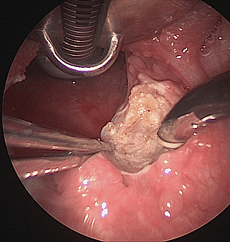

COBLATION Assisted Surgeries

A minimally invasive, low thermal technology for effective dissection and removal of tissue, COBLATION Technology has been used for ENT procedures such as tonsillectomy, turbinate reduction, laryngeal lesion debulking and soft palate.

While conventional electrosurgical devices use high temperatures to remove and cut tissue, our COBLATION Technology creates a controlled, stable plasma field to precisely remove tissue at a low relative temperature, resulting in minimal thermal damage to surrounding soft tissues. Its features include very limited depth of thermal penetration; minimal collateral tissue damage; localised effect; and controlled, volumetric tissue removal. Coblation is often preferred for its ability to reduce surgery duration and pain, minimise bleeding, and speed up recovery times in patients undergoing certain types of surgery.